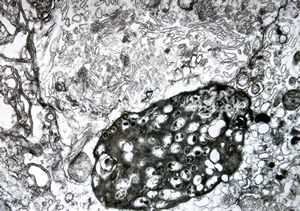

Whipple disease